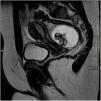

We present the case of a patient aged 14 years assessed in the emergency department for colicky pain in the right flank radiating toward the hypogastrium. The urinalysis was normal, and since the presentation was compatible with renal colic, an abdomen radiograph was performed (Fig. 1).

Ovarian tumours are rare in children, amounting to 1% to 5% of total paediatric tumours. Up to 90% of paediatric ovarian tumours are germ cell tumours, and the most frequent type is mature cystic teratoma (55%–70% of ovarian tumours in paediatrics).1,2 Ovarian mature cystic teratomas are benign tumours that can develop at any age, but the incidence peaks in the second and third decades of life. They arise from at least 2 of the 3 germ layers, and the contents are most frequently of ectodermal origin (hair, fat, teeth, skin…).2 Most patients are asymptomatic at diagnosis, with detection of the teratoma as a chance finding, but patients may develop abdominal pain, a palpable mass, complications such as ovarian torsion or rupture and even paraneoplastic syndromes, although the latter is very rare. Up to 10% of paediatric cases are bilateral.3 The initial diagnosis is made by abdominal ultrasound, in which the most common appearance is a cystic lesion with posterior shadowing (Rokitansky nodule). The evaluation is usually completed with an MRI scan to measure the mass more accurately and determine its relationship with adjacent structures.2 Approximately 50% have calcifications and up to 22% contain teeth detectable by imaging.4 Therefore, the detection of features with calcification density or shaped like a tooth in an abdominal X-ray may be key in the diagnosis of teratoma.